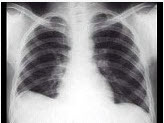

男,23岁,胸闷伴胸痛1月余,胸片如图,最可能的诊断为()

A . 右膈膨升

B . 右下肺盘状不张

C . 正常胸片

D . 右侧肺底积液

E . 右侧膈下脓肿